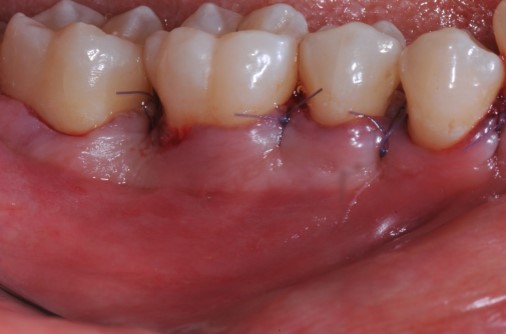

11/22 - Coronal advancement of the flap and suturing to achieve primary wound closure. Buccal view.

Deep intrabony defects treated using Straumann® Emdogain® - Dr. M. Stefanini